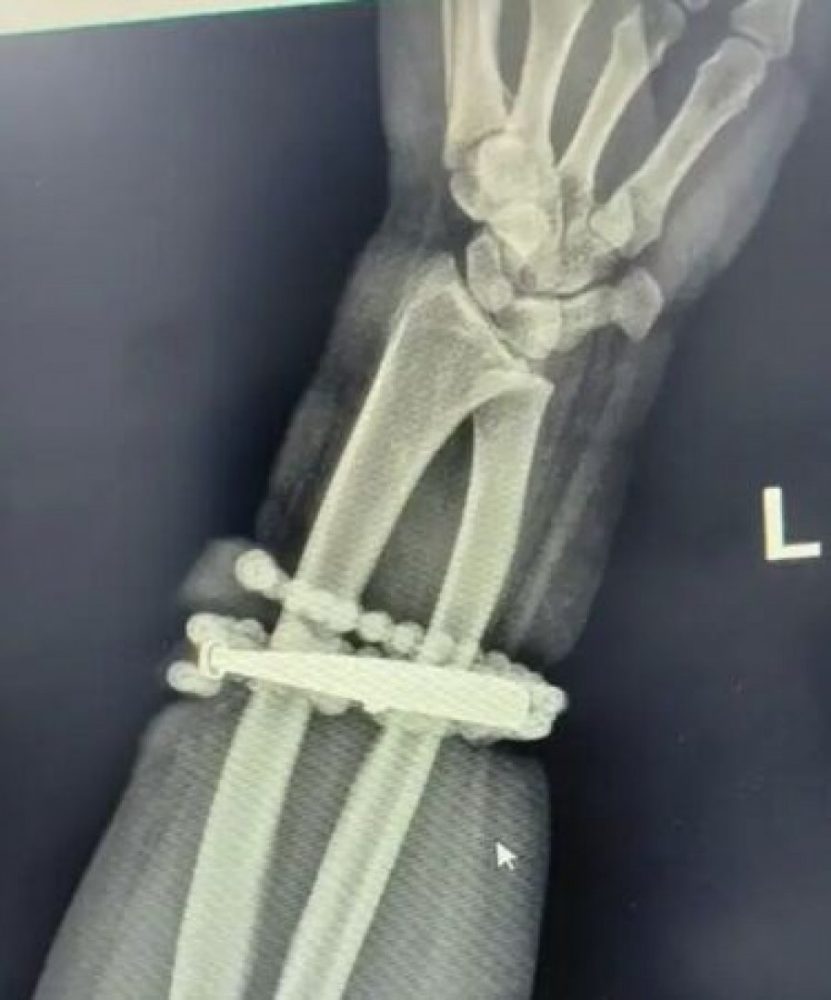

医生检查发现,手镯的长期压迫与摩擦造成皮下感染与肉芽组织增生,手镯已成为“体内异物”,若不及时取出,感染可能扩散,引发更严重后果。

经过一个多小时的手术,医生成功将手镯与佛珠从增生组织中取出,并进行清创与引流处理。所幸女子术后恢复顺利,目前已康复出院。